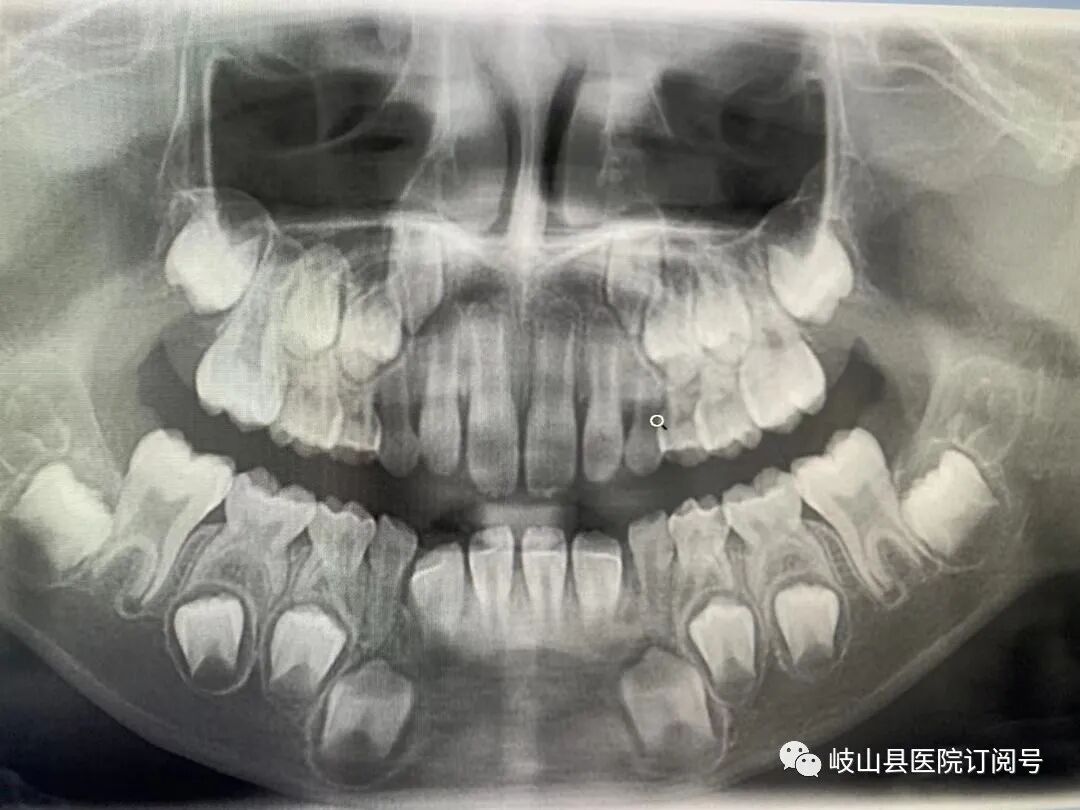

卡瓦CBCT即卡瓦口腔颌面锥形束CT(cone beam computed tomography),其基本原理是X线发生器以较低的射线量(通常球管电流在10毫安左右)围绕投照体做环形数字式投照,然后将围绕投照体多次数字投照后“交集”中所获得的数据在计算机中“重组”,进而获得高清三维图像。卡瓦X-TREND“三合一”CBCT即具有口腔曲面断层片、头颅侧位定位片和多功能CT三种拍摄功能,满足了口腔临床诊断的所有需要。

是目前国际最先进的口腔专用CT,在业界被誉为神奇的“慧眼”,具有扫描快、范围大、精度高、应用广、放射量极低的特点。可以通过其强大的处理软件功能以及面部匹配技术迅速形成清晰逼真的三维图像,较传统CT对于牙齿及颌骨组织的结构成像质量更好,彻底解决了口内牙片机、口腔全景机等口腔X射线设备影像重叠、畸变的问题,可以便捷直观地发现多种牙齿隐患问题,为口腔医生提供了精准的诊断与治疗依据。

卡瓦CBCT广泛应用于口腔各个领域:口腔颌面外科方面用于肿瘤、囊肿的范围及与上颌窦及下颌神经管的关系,颌骨骨髓炎的诊断,骨折的诊断及术前指导,阻生智齿的诊断及拔除指导,多生牙及埋伏牙的定位及毗邻关系,颞下颌关节病的诊断等;牙体牙髓方面可以清晰观察根管的数目及形态、能够发现变异的细小根管、早期的根尖炎症、牙根折裂等情况;牙周病方面可以确定牙周病的病变程度及指导治疗;牙列错颌畸形矫治方面用于研究颅面生长发育,诊断分析、矫治设计、前后对比,头影测量等;口腔种植方面涵盖了种植牙的每一个种植细节,提供了可靠的理论依据,确保种植牙手术的成功率。(口腔科  陈亚萍)